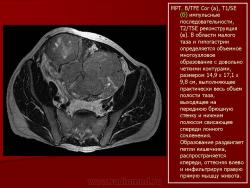

Онкология. Фибросаркома забрюшинного пространства. +

Фибросаркома забрюшинного пространства.